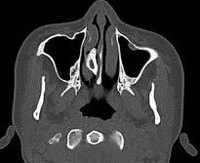

Магнитно-резонансная томография или КТ околоносовых пазух может определить местонахождение назального камня, его размеры, а также его отношение к пазухам. Рентгенография PPN отражает расположение только радиоактивных тел и состояние костных структур.